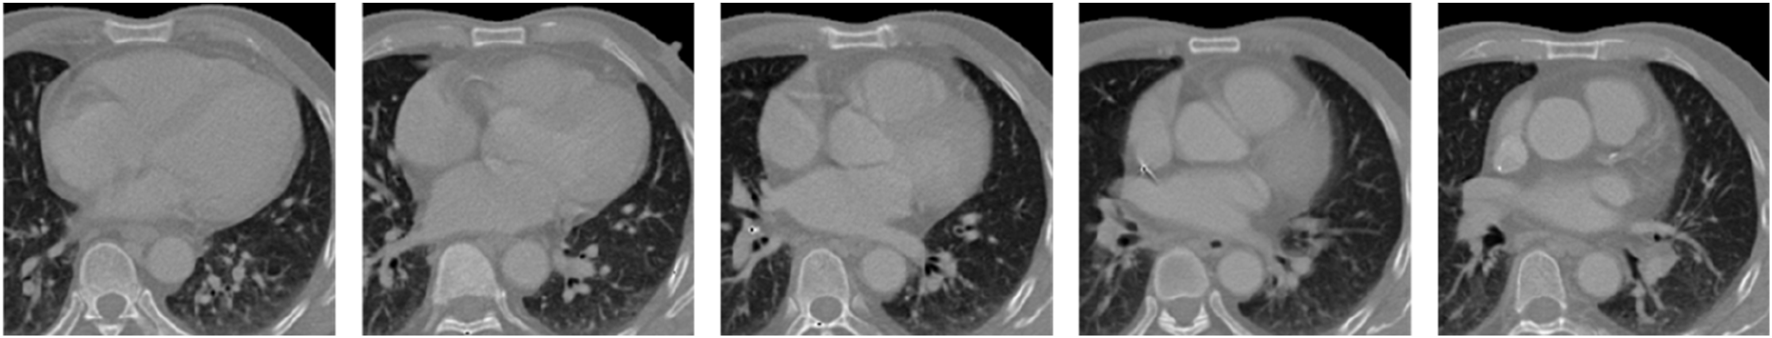

Cardiac substructures present several technical challenges in CT imaging, including heterogeneous grayscale intensities, poorly defined boundaries, irregular morphological features, and positional variability. Adjacent substructures often have similar grayscale values, resulting in low contrast, while some are connected via blood inflow pathways and differ significantly in size. Moreover, cardiac morphology and spatial orientation vary considerably across individuals, and even within the same subject over time or across imaging planes (as illustrated in Figure 2). Due to the inherent limitations of medical imaging modalities and tissue-specific properties, images are susceptible to artifacts such as noise and motion-induced distortions. These intrinsic challenges pose significant difficulties for accurate reconstruction of cardiac substructures.

FIGURE 2

CT slice sequence of cardiac substructures.